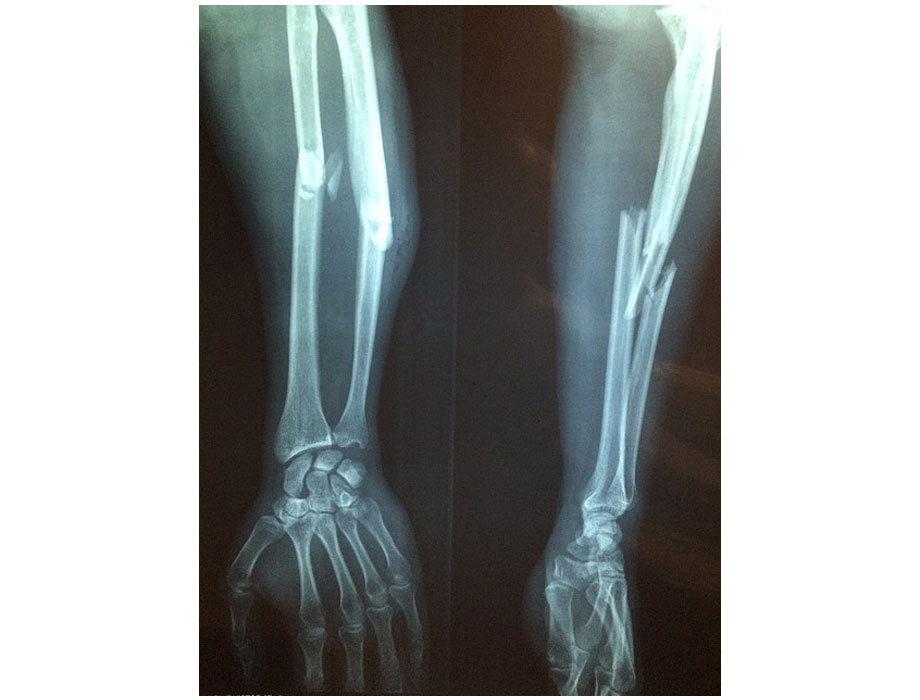

El acuerdo permitirá a Zimmer Biomet acceder a los implantes quirúrgicos y equipos de Paragon 28, utilizados en el tratamiento de dolencias del pie y el tobillo, además de fortalecer sus negocios en fracturas, traumatismos y reemplazo de articulaciones.